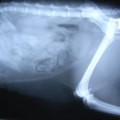

ペルシャ猫 11ヶ月齢 雄

他院にて左大腿骨遠位の成長板骨折(salter-harrisⅠ型)が認められており、治療相談を目的として来院。当院にて、キルシュナーワイヤーを用いたピンニングにより骨折部位の整復を行いました。術後の経過は良好で、現在も経過観察中です。

術前レントゲン

術後レントゲン